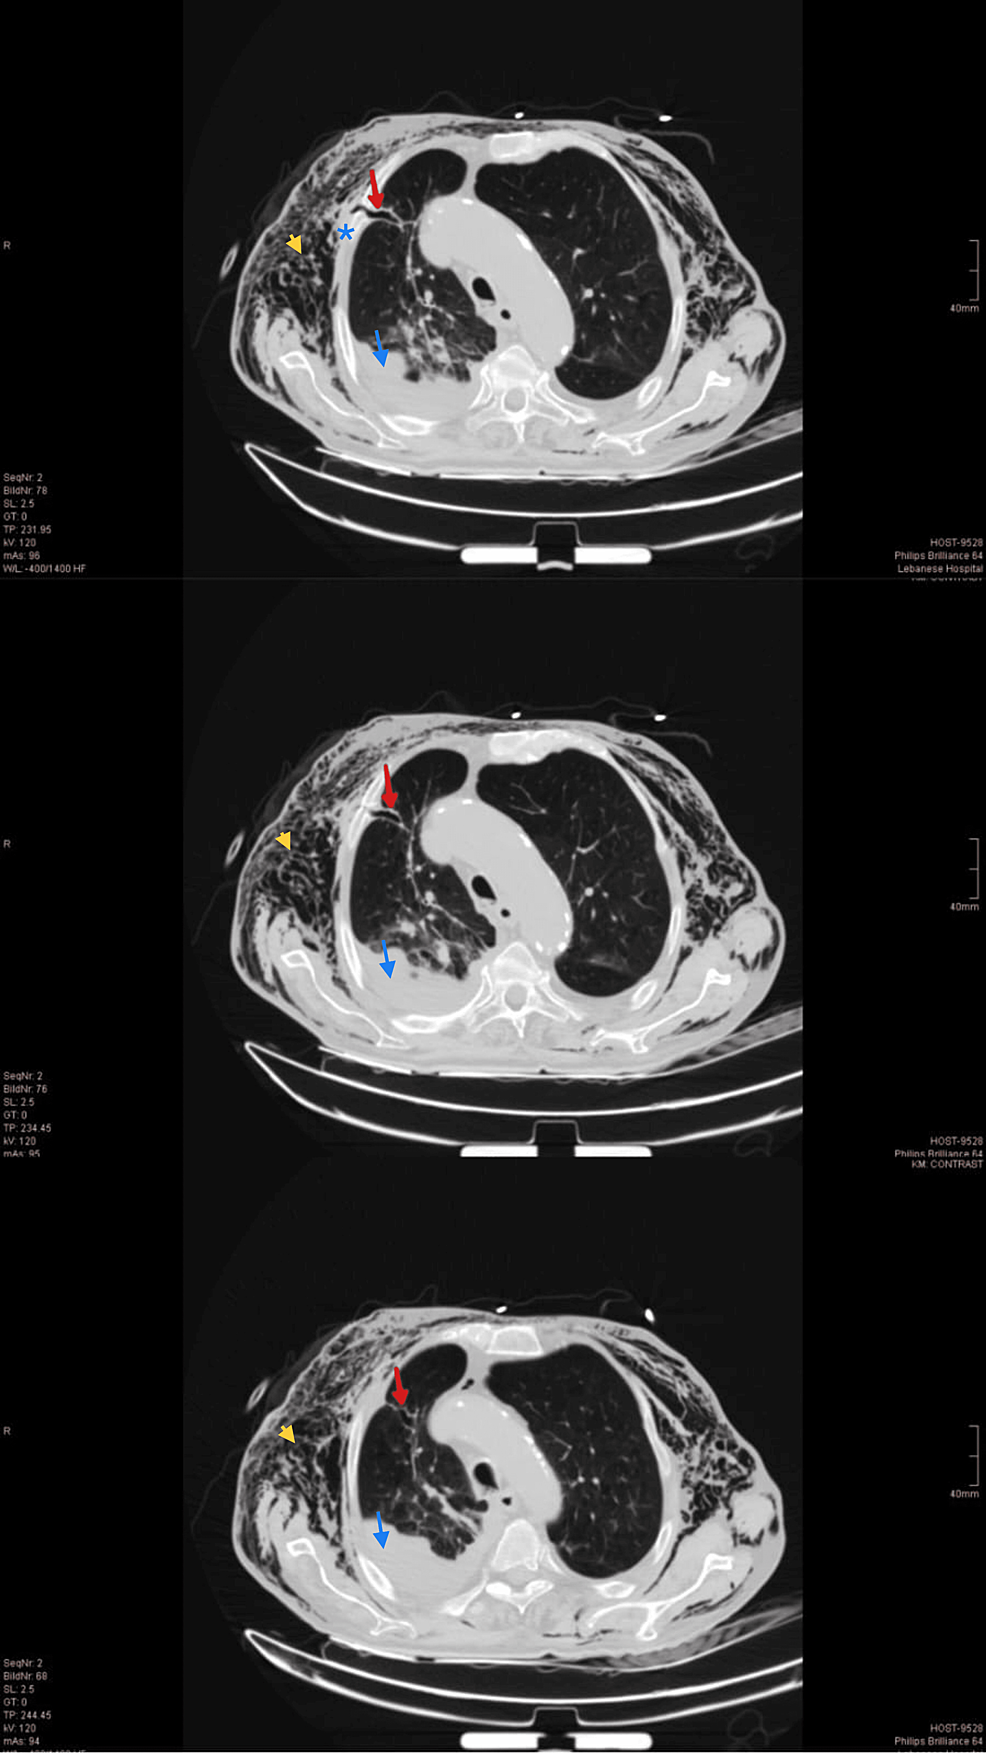

Patient with multiple rightsided rib fractures, flail chest Rib Fracture With Subcutaneous Emphysema [9] in fact, 27% of patients who have rib fractures also have. ct of the chest shows pneumomediastinum (blue arrow), left apical pneumothorax (pink arrow), and subcutaneous emphysema (red. The main symptoms are edema and. learn about the causes, symptoms, diagnosis, and treatment of rib fractures, which are common injuries. the most common cause of se was. Rib Fracture With Subcutaneous Emphysema.

Subcutaneous Emphysema. Axial CT 3, annotated. Rib Fractures. JETem Rib Fracture With Subcutaneous Emphysema learn about the causes, symptoms, diagnosis, and treatment of rib fractures, which are common injuries. subcutaneous emphysema is a condition in which air becomes trapped under the subcutaneous layer of the skin. [9] in fact, 27% of patients who have rib fractures also have. The main symptoms are edema and. subcutaneous emphysema is often observed by clinicians. Rib Fracture With Subcutaneous Emphysema.